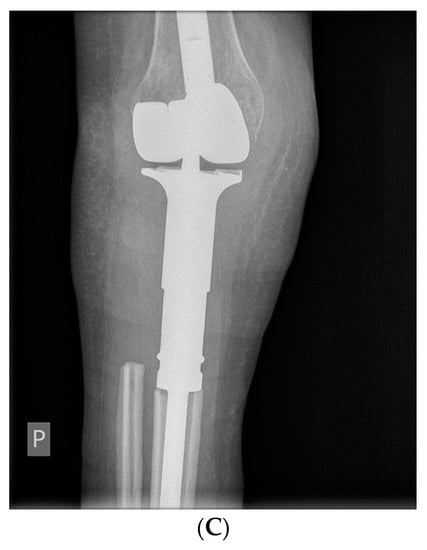

- Rutkowski, P.; Ferrari, S.; Grimer, R.J.; Stalley, P.D.; Dijkstra, S.P.D.; Pienkowski, A.; Vaz, G.; Wunder, J.S.; Seeger, L.L.; Feng, A.; et al. Surgical Downstaging in an Open-Label Phase II Trial of Denosumab in Patients with Giant Cell Tumor of Bone. Ann. Surg. Oncol. 2015, 22, 2860–2868. [Google Scholar] [CrossRef] [PubMed]

- Traub, F.; Singh, J.; Dickson, B.; Leung, S.; Mohankumar, R.; Blackstein, M.E.; Razak, A.R.; Griffin, A.; Ferguson, P.C.; Wunder, J.S. Efficacy of denosumab in joint preservation for patients with giant cell tumour of the bone. Eur. J. Cancer. 2016, 59, 1–12. [Google Scholar] [CrossRef]

- Van Langevelde, K.; McCarthy, C.L. Radiological findings of denosumab treatment for giant cell tumours of bone. Skelet. Radiol. 2020, 49, 1345–1358. [Google Scholar] [CrossRef] [PubMed]

- Branstetter, D.G.; Nelson, S.D.; Manivel, J.C.; Blay, J.-Y.; Chawla, S.; Thomas, D.; Jun, S.; Jacobs, I. Denosumab Induces Tumor Reduction and Bone Formation in Patients with Giant-Cell Tumor of Bone. Clin. Cancer Res. 2012, 18, 4415–4424. [Google Scholar] [CrossRef] [PubMed]